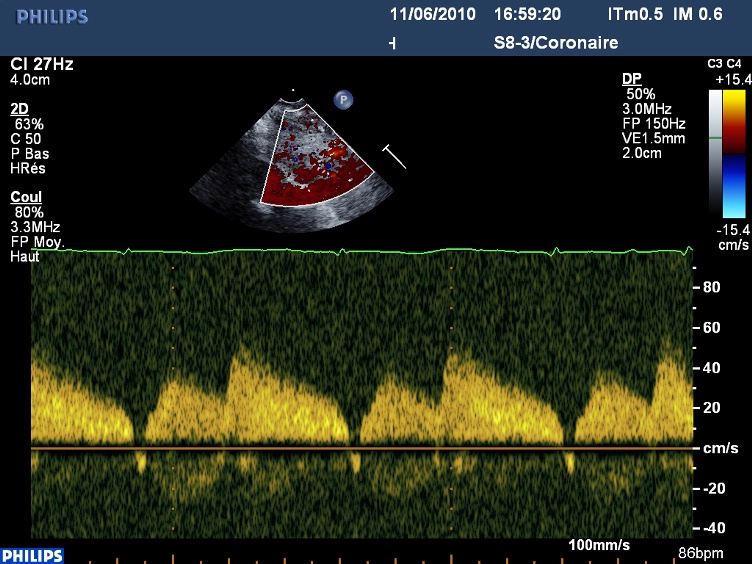

En Doppler, dans le pontage, un joli flux à prédominance diastolique :